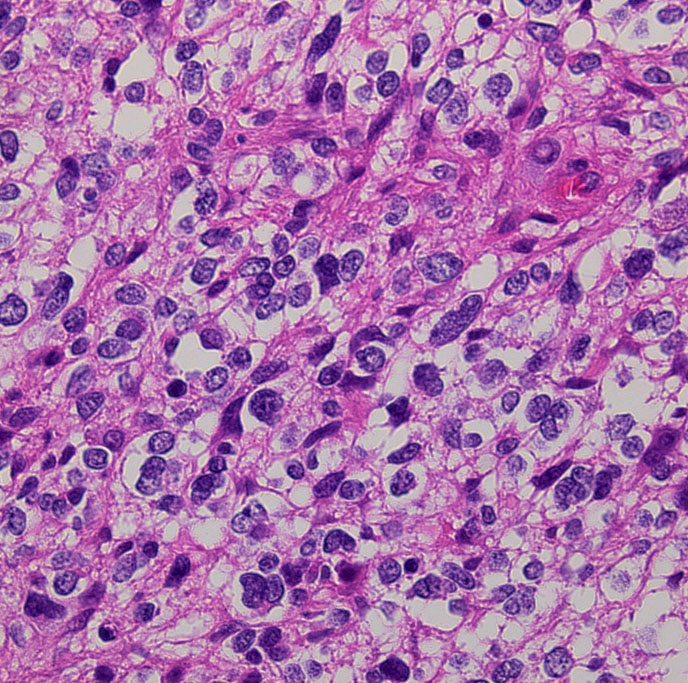

これは普通の病理組織診断です。これだけで膠芽腫という診断はつきます,

bizarre! 異様な細胞が混在しています。核多型が目立ち,多核巨細胞も混じる典型的な膠芽腫の像です。下の左の画像は血管内皮の肥厚 endovascular proliferationがあり,下の右のKi-67染色では核濃染像が多く核分裂能が高いことを示します。しかし,——